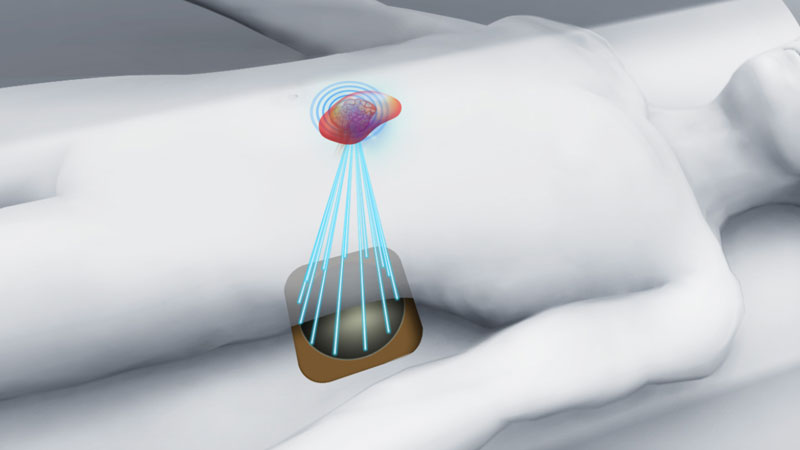

В Центре впервые внедрена неинвазивная технология дистанционной ультразвуковой абляции опухолей паренхиматозных органов HIFU

Проведены первые операции при миоме матки, опухолях печени, поджелудочной железы, надпочечников и др.